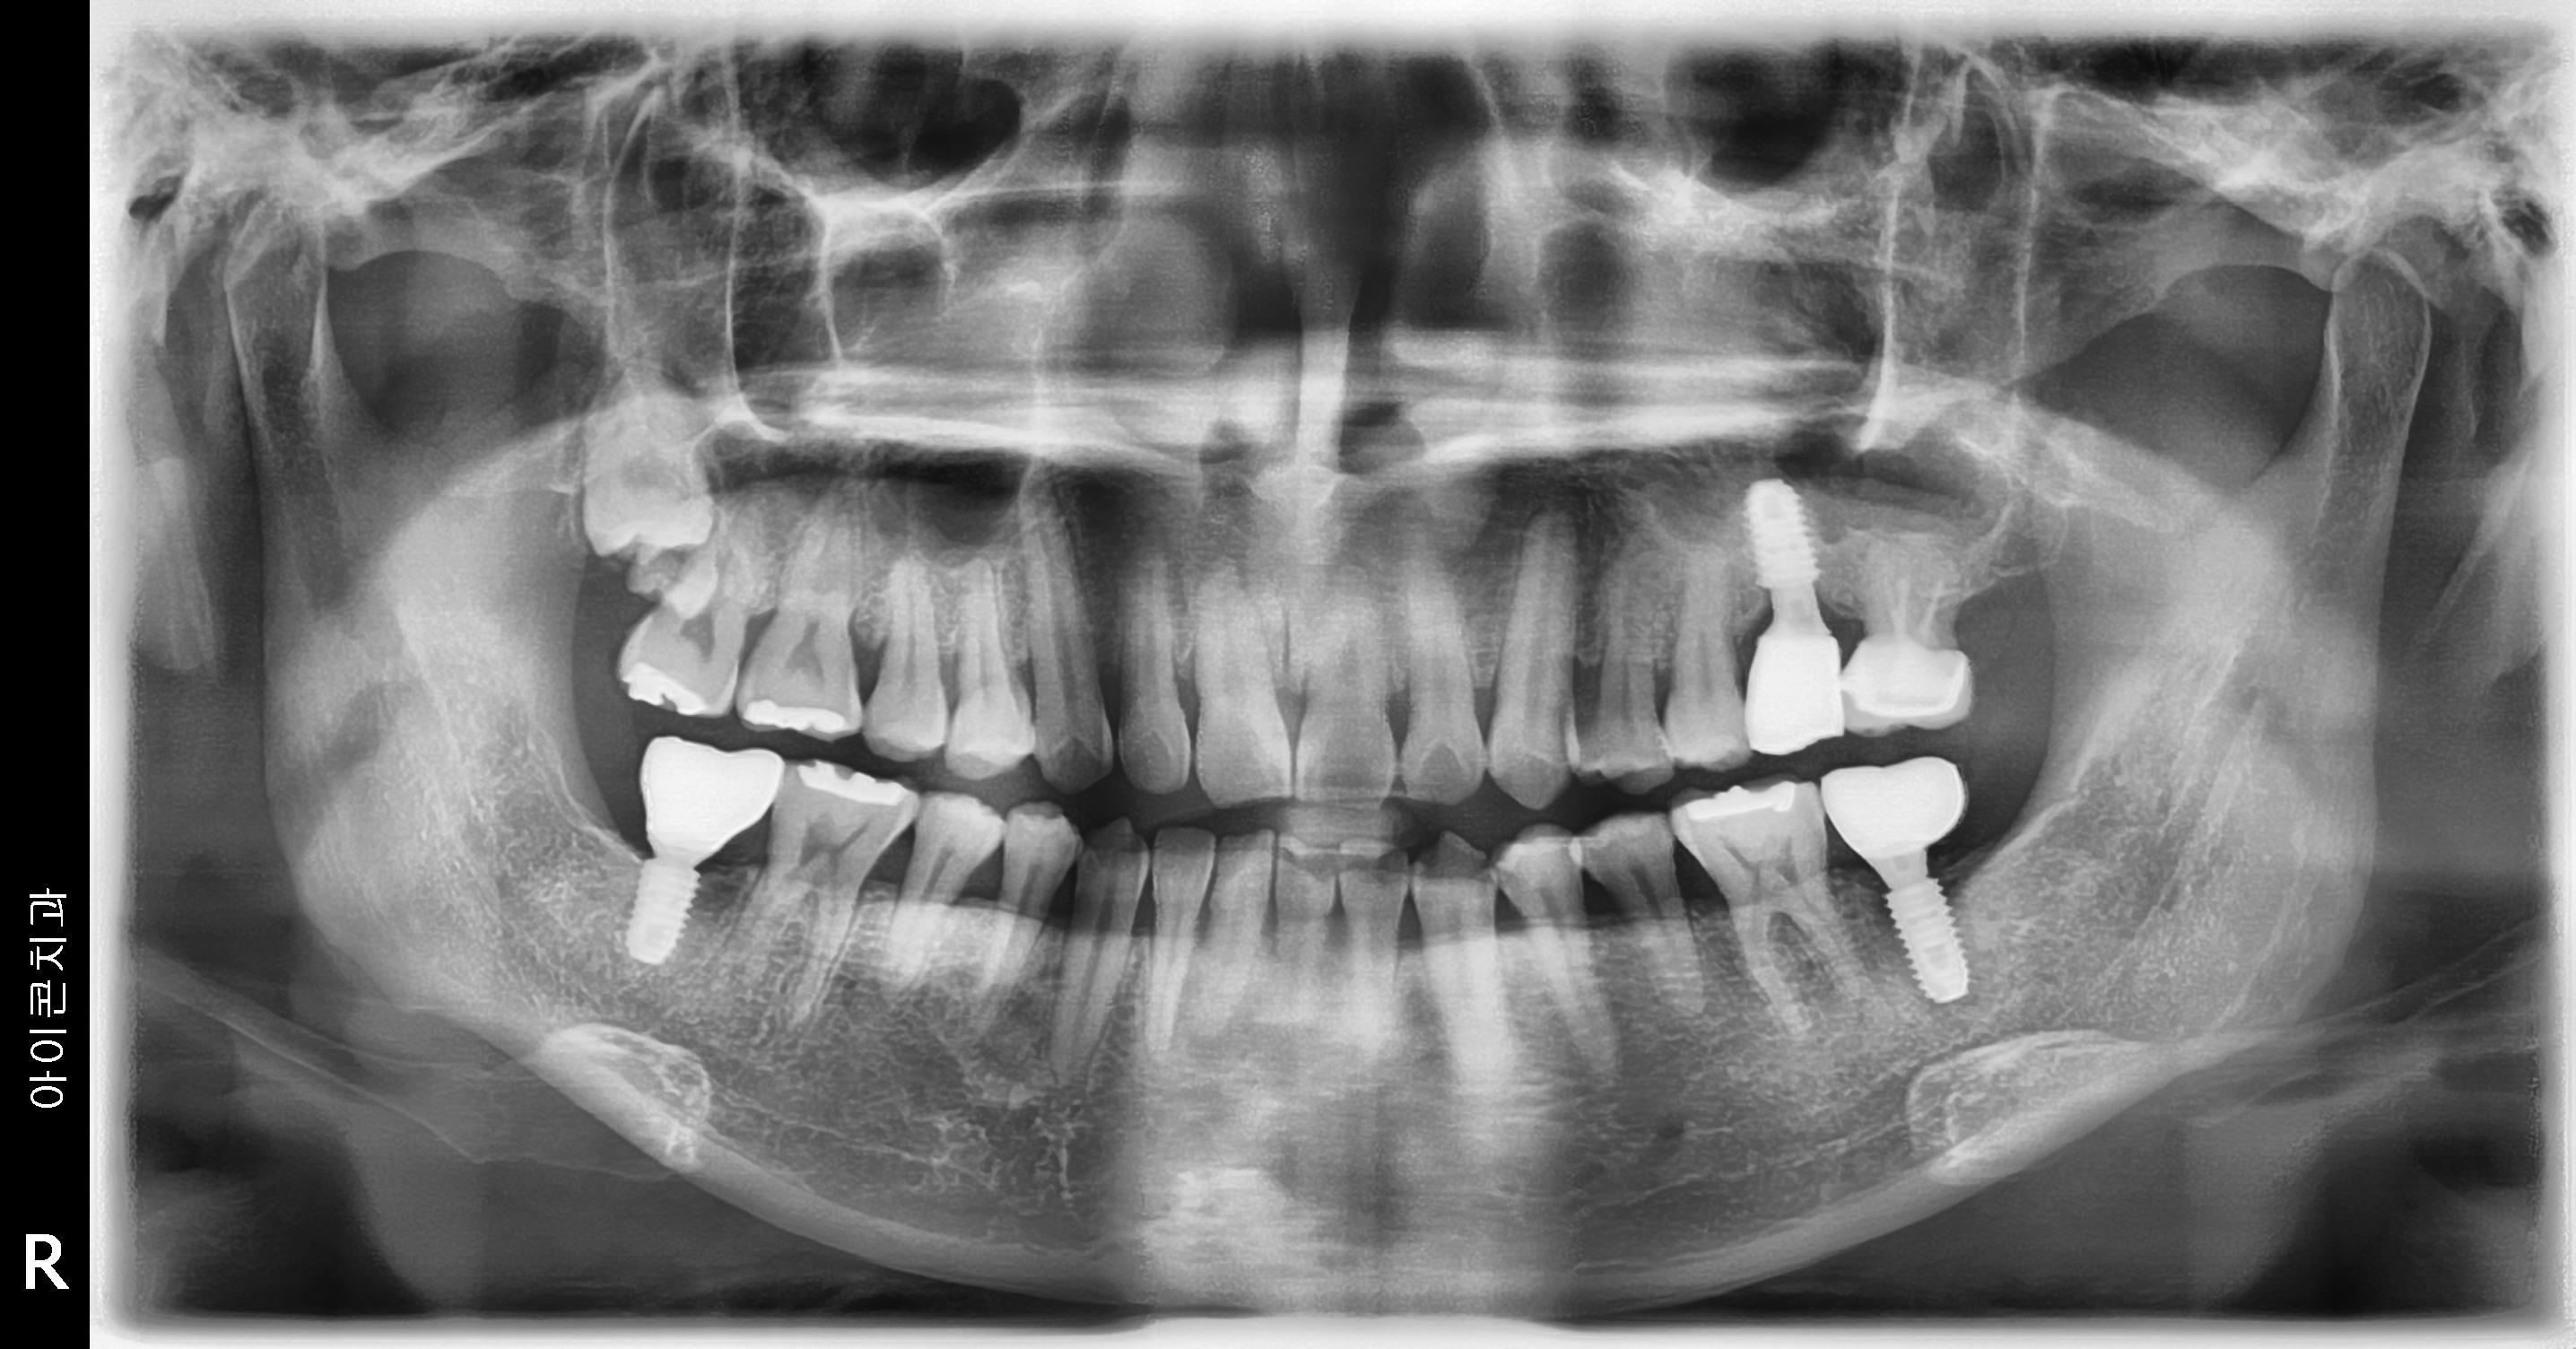

수술 전

수술 후

하악 임플란트 식립사례

전후사진